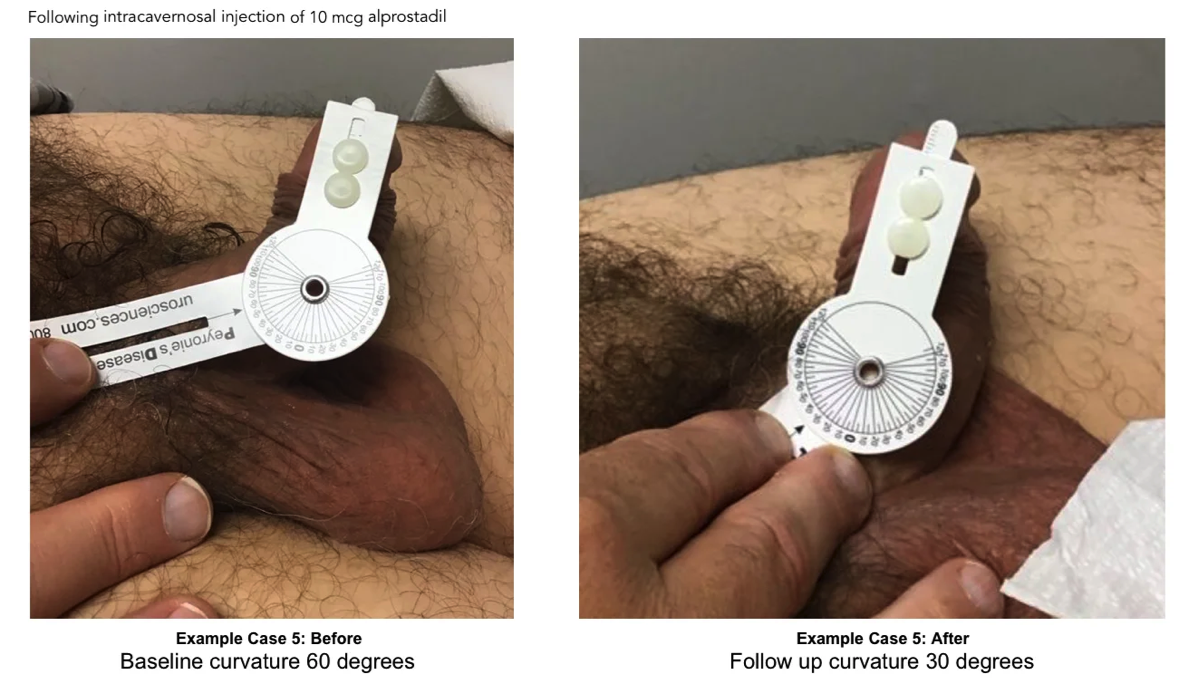

Degree of penile curvature was recorded during the initial and follow up duplex doppler ultrasound by use of a protractor. In many cases, but not all, pictures were provided with protractor showing measurement of current curve. Value of curve was accepted with or without confirmation picture.

3.2 ExoSurge treatment change in curve

A comparison was made between initial duplex doppler ultrasound and final/intra-treatment ultrasound as some patients were still undergoing treatments. Of the initial 50 patients with a curve, 36 of those patients also had a venous leak. Of the 50 patients with a curve, 17 of them had a curve less than 30 degrees with 12 of those with a venous leak. Thirty-three of the 50 had a curve greater than 30 degrees, of which 24 had a venous leak. The final study review of the 50 pts who were initially found to have a curve, 8 of those patients had no curve at all. Of the original 33 with a curve greater than 30 degrees, this number decreased to only 20 patients. On the initial study only 17 patients had a curve less than 30 degrees and this increased to 22. Therefore, 8 patients completely corrected to no longer have a curve and 5 had reduced significantly, one patient's curve increased by 8 degrees. A 58% reduction in curve was noted for the entire group who showed a decrease in the degree of curve. Fourteen percent of patients showed no improvements with the curve.

During the time reviewed, we found only 24 patients still receiving therapy at the final date for review. The individual average improvement for these patients at the end date was 60%. Of the 26 patients no longer participating in treatment, there was an individual average

Figure 3 Improvements Average Per Patient

improvement of 55% to their curvature. This change is congruent with our observations showing the largest change in curvature realized toward the end of therapy.

Before and After Peyronie's Treatment Photos

Have you ever Googled "before and after Peyronie's treatment photos"? The only images you'll find are gut wrenching photos taken midway through plication or "incision & graft" Peyronie's surgery.

Following are baseline and follow up images of Peyronie's patients following treatments with ExoSurge®. We hope to share many more soon. Unfortunately, patients must grant us permission to release these photographs, and few are willing to do that.